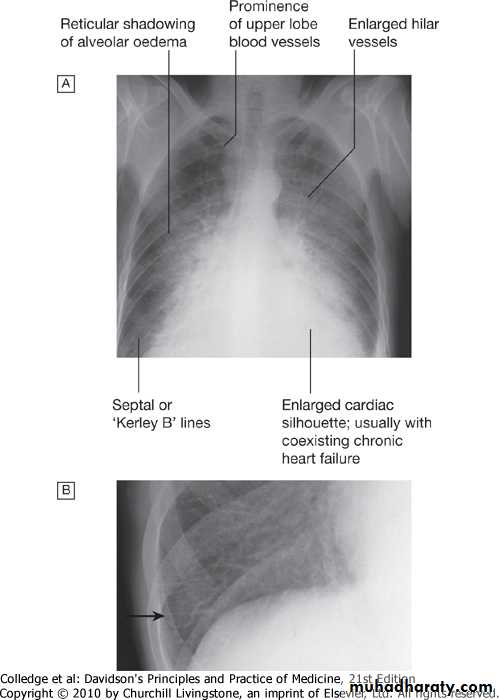

• CXR (CARDIOMEGALY ,PULM.EDEMA)